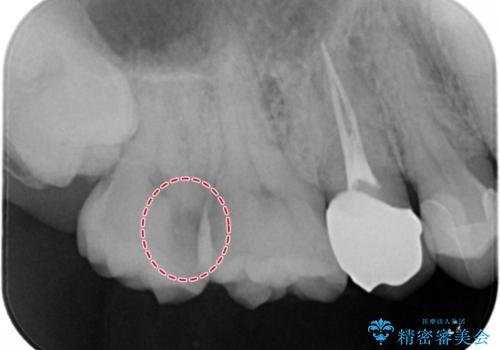

奥歯の深い場所に二次う蝕が確認されました。

歯肉を整理し、今後同じことを繰り返さないよう精度の良いゴールドアンレーで修復処置を行いました。